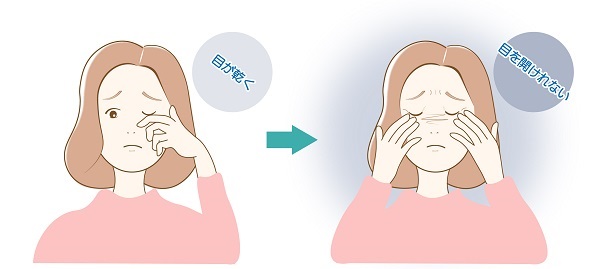

眼瞼けいれん

まぶたを閉じる筋肉(眼輪筋)の持続的な収縮によって、意に反して目を閉じてしまう(閉じていると楽な)、40歳以上の女性に多い病気です。瞬きの増加、眩しさといった主症状に加え、目の乾燥、ショボショボ感、まぶたのぴくぴくとした痙攣などが見られます。当院では、神経眼科にて眼瞼けいれんの専門的な治療を行っています。